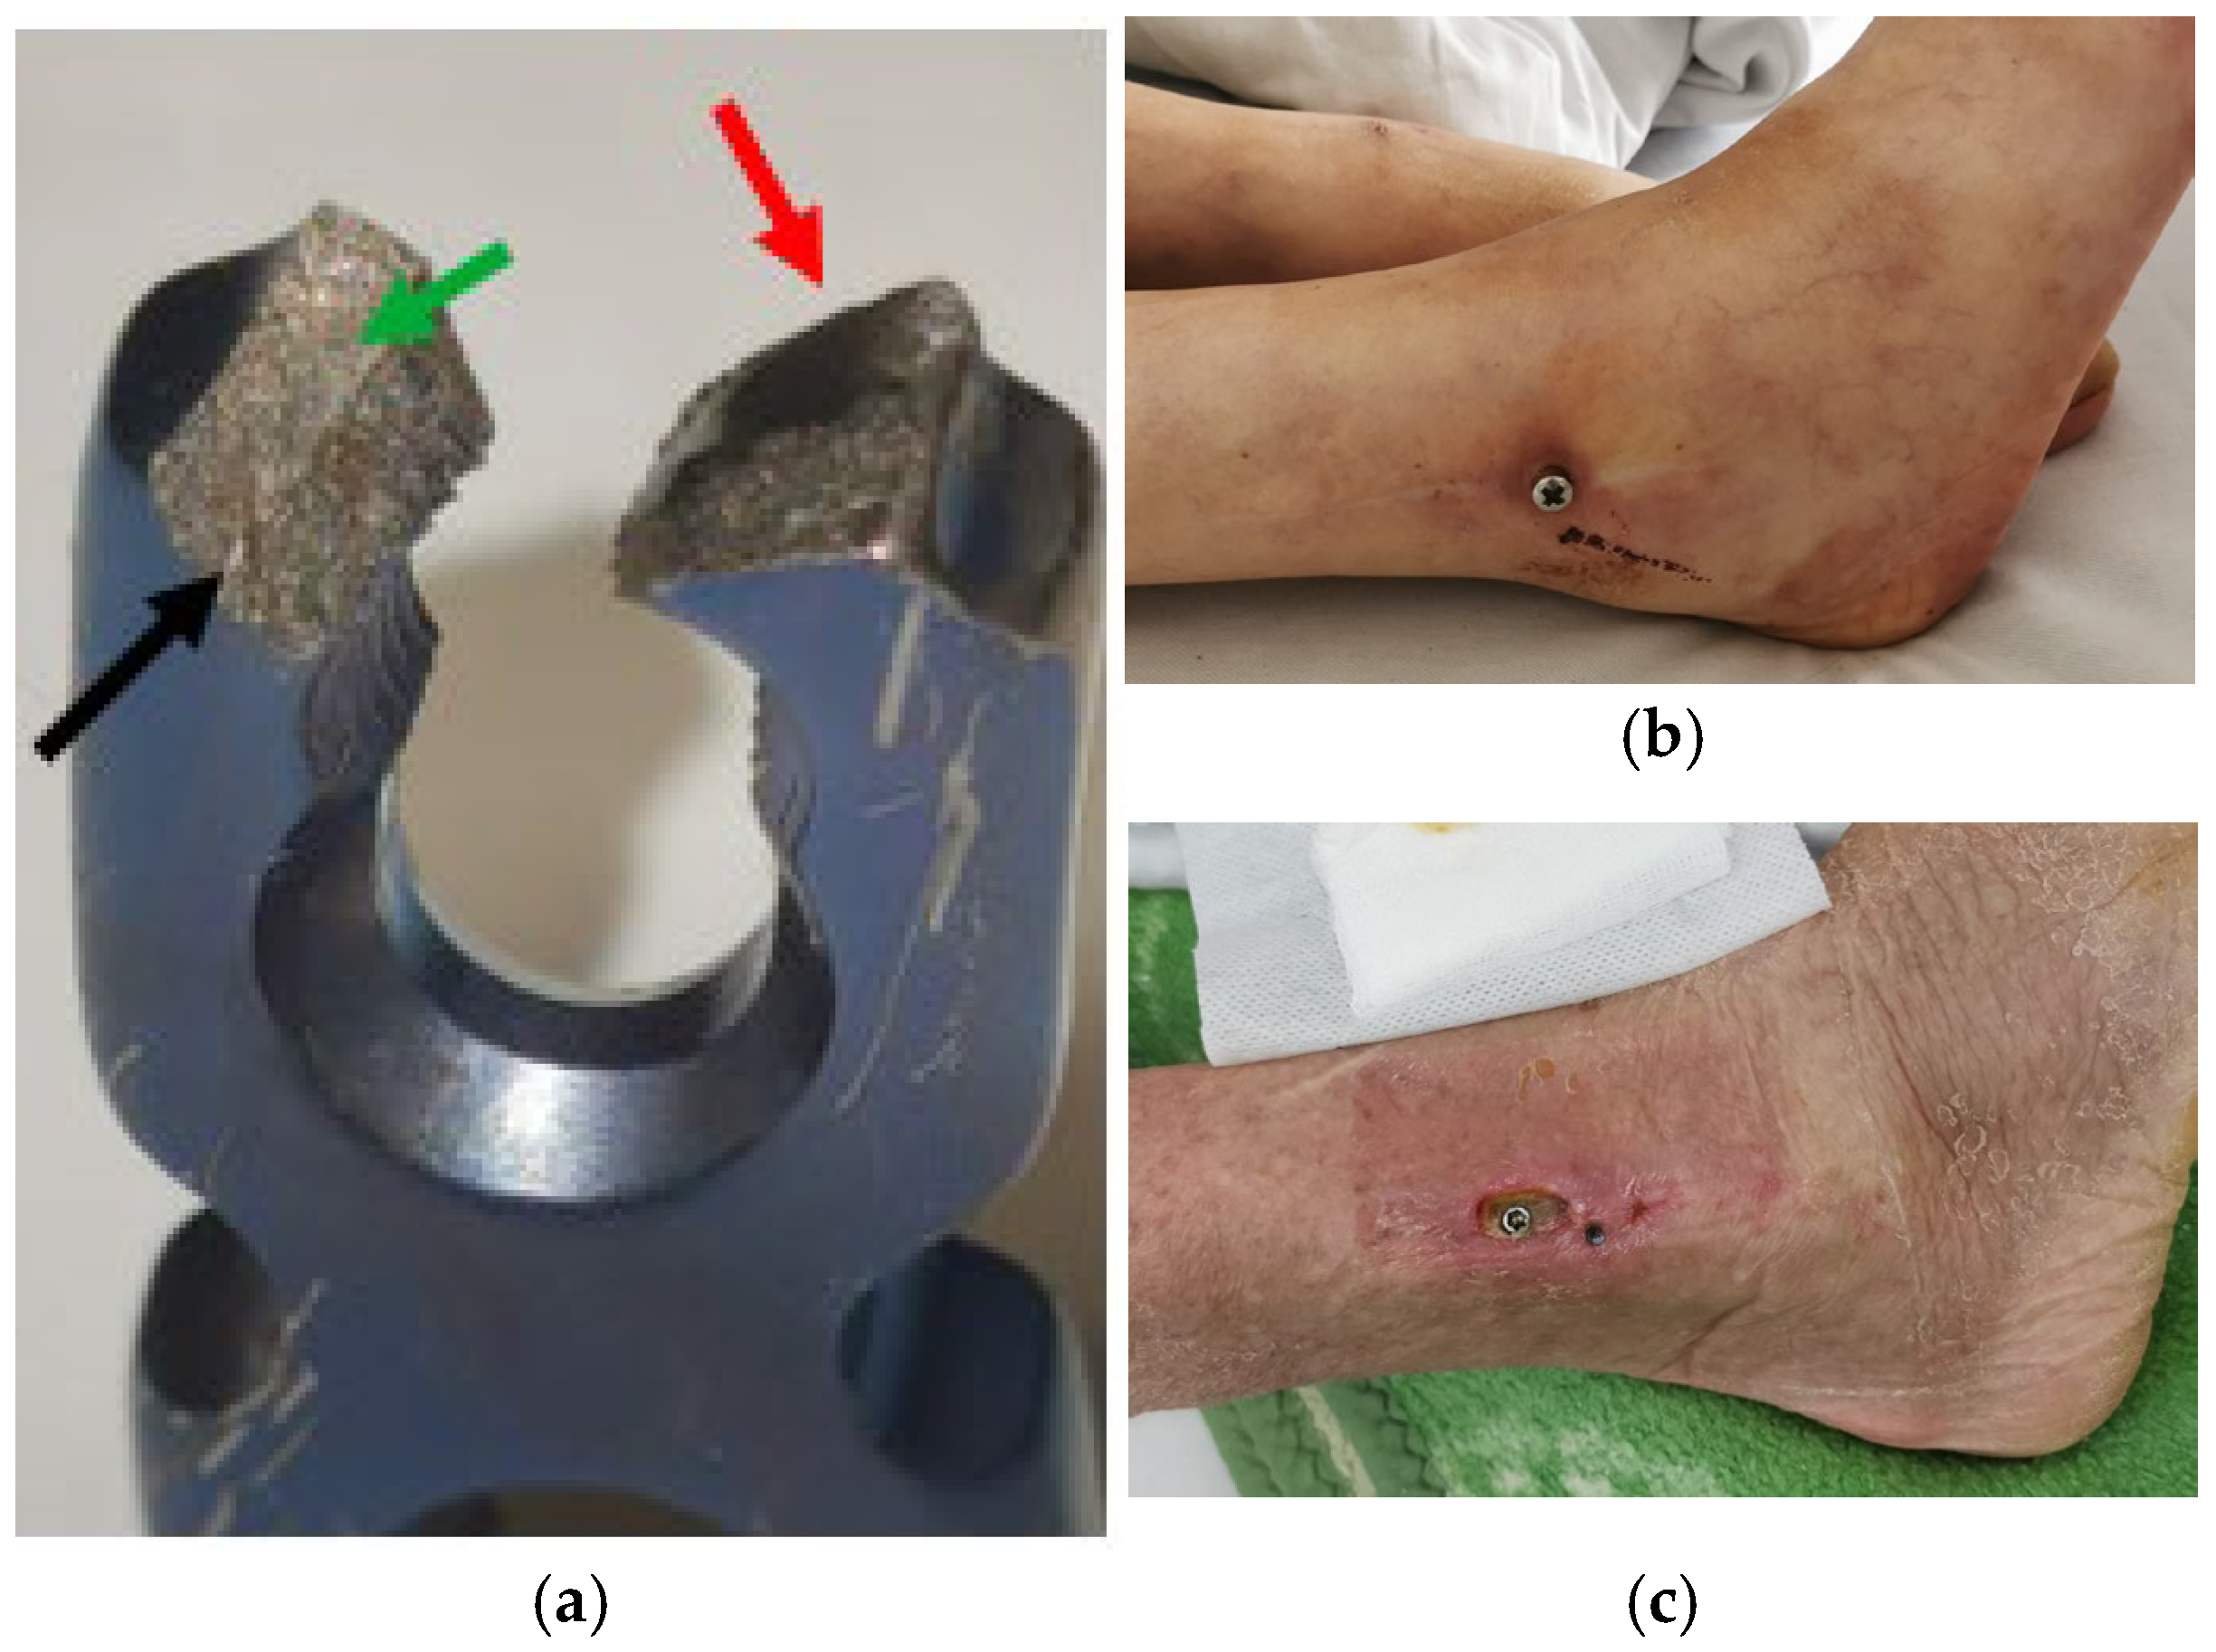

| Element | Effects and Uses | Toxicity | Irritation | Allergy | Mitigation Strategies | Ref. |

|---|---|---|---|---|---|---|

| Gold (Au) | Used in medical and dental implants due to its non-corrosive nature; historically used in jewellery and coins; possesses some antimicrobial properties. | Considered non-toxic; does not corrode; is bioinert in most cases. | Very low; does not commonly cause irritation. | Rare but possible sensitization reactions in some individuals. | Use inert forms when possible. Limit exposure to reactive gold compounds. Monitor for signs of allergic reactions in medical settings. | [13] |

| Silver (Ag) | Used in dental implants, wound dressings, and coatings for medical devices due to its antimicrobial properties. | Low toxicity, but long-term exposure can lead to argyria (blue-grey skin discoloration). | Generally low; can cause irritation, if absorbed in excess. | Rare, but silver allergies have been reported. | Adhere to regulated dosages in medicinal applications. Ensure proper handling in industrial processes to avoid ingestion or prolonged exposure. | [13] |

| Copper (Cu) | Used in alloys such as bronze and brass; has bactericidal properties; is currently not used for dental or orthopaedic applications, but is still in use in gynaecology (contraceptive spirals). | Toxic in high amounts; can cause liver and kidney damage (Wilson’s disease) and neurological symptoms. | High irritation potential; copper salts can cause skin and mucosal irritation. | Can trigger contact dermatitis, particularly in individuals sensitive to metal jewellery. | Monitor dietary and environmental copper levels. Apply chelation therapy in poisoning cases. Control contamination in water supplies and industrial settings. | [13] |

| Iron (Fe) | Essential for red blood cell production; used in stainless steel implants, surgical instruments, and devices. | Generally safe, but excess iron (hemochromatosis) can lead to organ failure and oxidative stress. | Mild; iron supplements may cause gastrointestinal irritation. | Rare, but intravenous iron infusions may trigger allergic reactions. | Use iron chelators (e.g., deferoxamine) and phlebotomy for overload conditions. Regulate iron supplementation and monitor body iron levels. | [38] |

| Nickel (Ni) | Common in stainless steel and orthopaedic implants; is an austenite stabilizer; improves corrosion resistance and the strength of an alloy; is highly allergenic. | Moderate to high toxicity; nickel exposure can lead to systemic toxicity, organ damage, and carcinogenic effects. | Strong irritant; causes skin irritation and can provoke chronic conditions like eczema. | One of the most common metal allergens; causes nickel dermatitis, itching, and rashes. | Limit exposure (especially in sensitized individuals) through substitution in products. Use appropriate personal protective equipment (PPE) in industrial settings. | [13,16] |

| Chromium (Cr) | Found in stainless steel, dental, and orthopaedic implants; improves corrosion resistance. | Hexavalent chromium is highly toxic and carcinogenic; can cause lung and kidney damage. | Strong irritant; chromate salts cause severe skin and respiratory irritation. | Can provoke immune responses and hypersensitivity reactions in some individuals. | Replace or reduce Cr(VI) with Cr(III) when possible. Enforce strict industrial controls and PPE. Implement remediation strategies for contaminated sites. | [16,38] |

| Cobalt (Co) | Mechanically very hard; used in cobalt–chromium-molybdenum (CoCrMo) alloys to manufacture various medical implants; is also essential in vitamin B12 (cobalamin). | Toxic in high exposure; linked to cardiomyopathy, neurological disorders, and thyroid dysfunction. | Moderate; can cause dermatitis, rashes, and respiratory irritation. | High allergenic potential; can trigger cobalt dermatitis and asthma. | Enforce industrial hygiene practices and limit airborne exposure. Use PPE and continuous monitoring in occupational settings. | [13,16] |

| Molybdenum (Mo) | Strengthens stainless steel and CoCrMo alloys; is an essential trace dietary element. | Low toxicity; rare cases of molybdenum poisoning exist, often occupational. | Mild irritant, particularly in dust or fume form. | Rare allergic reactions, though not commonly recognized as an allergen. | Monitor exposure in occupational environments. Ensure balanced dietary intake to avoid imbalances with copper levels. | [13,16] |

| Aluminium (Al) | Used in alloys, implants, vaccines, antacids, and food packaging; is lightweight and corrosion-resistant. | Generally considered non-toxic, but possible links between aluminium poisoning and Alzheimer’s disease and neurodegeneration are debated. | Mild; can cause skin irritation and granulomas, when implanted. | Possible, but rare aluminium hypersensitivity reactions exist. | Reduce exposure through water treatment and controlled use in consumer products. Use alternative materials in medical applications (e.g., dialysis fluids). | [16,38] |

| Titanium (Ti) | Used extensively in orthopaedic and dental implants; is bioinert and corrosion-resistant. | Low toxicity, but some concerns over long-term accumulation in tissues. | Low irritation; metallosis can occur in rare cases around implants. | Rare cases of titanium hypersensitivity reported, leading to implant rejection. | Control nanoparticle release in industrial settings. Use adequate ventilation and PPE to limit inhalation exposure. | [13] |

| Lead (Pb) | In the past, used in dental amalgams and anti-infectious medicines (i.e., syphilis); also used in paints, plumbing, and batteries but is highly toxic to humans. | Highly toxic; causes neurological damage, developmental disorders, kidney failure, and anaemia. | Strong irritant; can cause severe skin and mucosal inflammation. | Not typically allergenic, but exposure can affect the immune system. | Remove lead sources from environments (e.g., lead abatement programs). Apply chelation therapy when necessary. Enforce strict industrial and public health regulations. | [34] |

| Mercury (Hg) | In the past, used in dental amalgams and thermometers; is highly toxic. | Neurotoxic; affects the central nervous system, kidneys, and immune system. | Strong irritant; can cause burns, ulcers, and respiratory issues. | Rare, but mercury exposure can sometimes provoke immune reactions. | Limit consumption of high-mercury fish and control industrial emissions. Use chelation therapy for mercury poisoning. Monitor and remediate environmental contamination. | [38] |

| Strontium (Sr) | Used in bone-strengthening treatments (strontium ranelate) and some medical alloys. | Low toxicity; large amounts can disrupt calcium metabolism. | Mild irritant in high doses. | Rare, but can theoretically trigger immune responses. | Monitor and regulate industrial and environmental exposures. Remediate radioactive contamination and use safe handling practices. | [128] |

| Vanadium (V) | Found in some orthopaedic alloys; is considered for medical applications. | Moderate toxicity; excessive exposure can cause neurotoxicity and respiratory issues. | High irritation potential, particularly in airborne forms. | Rare, but sensitization reactions have been reported. | Limit exposure through strict industrial standards. Monitor environmental levels and enforce the use of PPE. | [9,79] |

| Niobium (Nb) | Used in orthopaedic implants to enhance biocompatibility. | Low toxicity; well-tolerated by human tissues. | Low irritation; does not commonly provoke adverse effects. | May reduce allergic reactions to other metals in alloys. | Follow standard industrial hygiene protocols. Monitor exposure where applicable and promote further research on long-term effects. | [53] |

| Antimony (Sb) | Historically used in medicine for antiparasitic and emetic treatments. | Toxic in excess; affects the liver, heart, and respiratory system. | Strong irritant; can cause skin inflammation and mucosal damage. | Possible allergic reactions, particularly in occupational exposure. | Employ strict industrial controls and proper PPE. Monitor air quality and ensure safe handling/disposal of antimony compounds. | [13] |

| Beryllium (Be) | Industrially used but highly toxic; in medicine, used as a radiographic dye (BaSO4). | Very toxic; causes lung disease (berylliosis) and is carcinogenic. | Strong irritant; beryllium compounds cause severe skin and respiratory inflammation. | Highly allergenic; can trigger chronic immune disorders (beryllium sensitization). | Implement rigorous industrial controls and respiratory protection. Substitute with less toxic materials when possible. Regular health screening for exposed workers. | [13,131] |